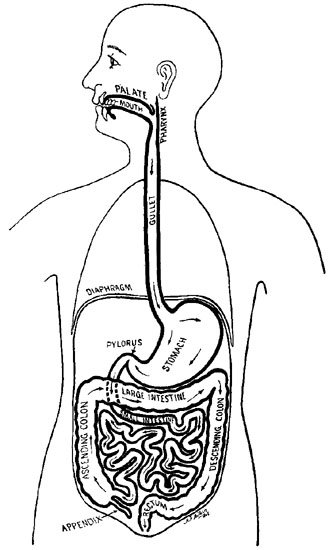

8 The Food Route in the Digestive System

How the Food Reaches the Stomach. Our body, then, has an opening, which we call the mouth, through which our food-fuel can be taken in. A straight delivery tube, called the gullet, or esophagus, runs down from the mouth to a bag, or pouch, called the stomach, in which the food is stored until it can be used to give energy to the body, just as the gasoline is stored in the automobile tank until it can be burned.

The mouth opening is furnished with lips to open and close it and assist in picking up our food and in sucking up our drink; and, as much of our food is in solid form, and as the stomach can take care only of fluid and pulpy materials, nature has provided a mill in the mouth in the form of two arches, of semicircles, of teeth, which grind against each other and crush the food into a pulp.

In this diagram the entire alimentary canal is shown enlarged, and the small intestine greatly shortened, in order to show distinctly the course of the food in the process of digestion.

In the bottom or floor of the mouth, there has grown up a movable bundle of muscles, called the tongue, which acts as a sort of waiter, handing the food about the mouth, {9}pushing it between the teeth, licking it out of the pouches of the cheeks to bring it back into the teeth-mill again, and finally, after it has been reduced to a pulp, gathering it up into a little ball, or bolus, and shooting it back down the throat, through the gullet, into the stomach.

The Intestines. When the food has been sufficiently melted and partially digested in the stomach, it is pushed on into a long tube called the intestine, or bowel. During its passage through this part of the food tube, it is taken up into the veins, and carried to the heart. From here it is pumped all over the body to feed and nourish the millions of little cells of which the body is built. This bowel tube, or intestine, which, on account of its length, is arranged in coils, finally delivers the undigested remains of the food into a somewhat larger tube called the large intestine, in the lower and back part of the body, where its remaining moisture is sucked out of it, and its solid waste material passed out of the body through the rectum in the form of the feces.

The Stomach—its Shape, Position, and Size. By means of muscular contraction, then, the gullet-elevator carries the food into the stomach. This is a comparatively simple affair, merely a ballooning out, or swelling, of the food tube, like the bulb of a syringe, making a pouch, where the food can be stored between meals, and where it can undergo a certain kind of melting or dissolving. This pouch is about the shape of a pear, with its larger end upward and pointing to the left, and its smaller end tapering down into the intestine, or bowel, on the right, just under the liver. The middle part of the stomach lies almost directly under what we call the "pit of the stomach," though far the larger part of it lies above and to the left of this point, going right up under the ribs until it almost touches the heart, the diaphragm only coming between.[3] This is one of the reasons why, when we have an attack of indigestion, and the stomach is distended with gas, we are quite likely to have palpitation and shortness of breath as well, because the gas-swollen left end of the stomach is pressing upward against the diaphragm and thus upon the heart and the lungs. Most cases of imagined heart trouble are really due to indigestion.

Digestion in the Stomach. Although usually a single, pear-shaped pouch, the stomach, during digestion, is practically divided into two parts by the shortening, or closing down, of a ring of circular muscle fibres about four inches from the lower end, throwing it into a large, rounded pouch on the left, and a small, cone-shaped one on the right. The gullet, of course, opens into the large left-hand pouch; and here the food is stored as it is swallowed until it has become sufficiently melted and acidified (mixed with acid juice) to be ready to pass on into the smaller pouch. Here more acid juice is poured out into it, and it is churned by the muscles in the walls of the stomach until it is changed to a jelly-like substance.

Digestion in the Small Intestine. The food-pulp now passes on into the small intestine, where it is acted upon {16}by two other digestive juices—the bile, which comes from the liver, and the pancreatic juice, which is secreted by the pancreas.

What does this great combination of powers in the pancreas mean? It means that we have now reached the real centre and chief seat of digestion, namely, the small intestine, or upper bowel. This is where the food is really absorbed, taken up into the blood, and distributed to the body. All changes before this have been merely preparatory; all after it are simply a picking up of the pieces that remain.

In general appearance, this division of the food tube is very simple—merely a tube about twenty feet long and an inch in diameter, thrown into coils, so as to pack into small space, and slung up to the backbone by broad loops of a delicate tissue (mesentery). It looks not unlike twenty feet of pink garden hose.

The Final Stage—the Journey through the Large Intestine. From the small intestine what remains of the food-pulp is poured into the last section of the food tube, which enlarges to from two to three inches in diameter. It is known as the large intestine, or large bowel. This section is only about five feet long. The first three-fourths of it is called the colon; the last or lowest quarter, the rectum, the discharge-pipe of the food tube. The principal use of the colon is to suck out the remaining traces of nourishing matter from the food and the water in which it is dissolved, thus gradually drying the food-pulp down to a solid or pasty form, in which condition it collects in a large "S" shaped loop of the bowel just above the rectum, until discharged.